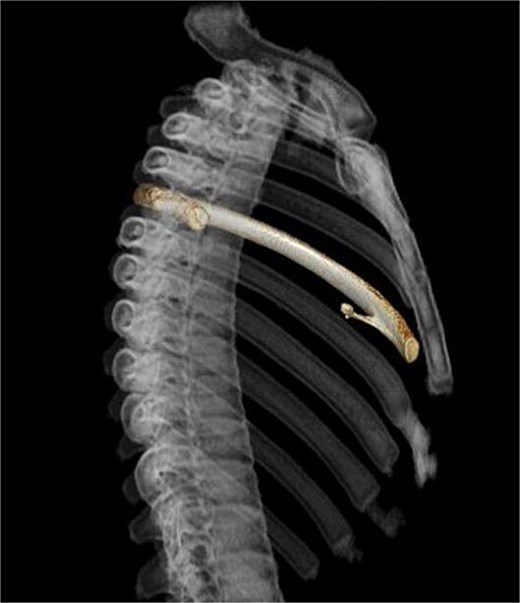

A 13-year-old boy presented with chest pain and dyspnea. There was no significant medical or family history. Chest radiography showed a left pneumothorax and opacity in the left middle lung field (Fig. 1). Computed tomography (CT) showed a left pneumothorax and a bony, pedunculated mass arising from the fifth rib. The cortical bone and bone marrow continued to move away from the fifth rib (Fig. 2). The mass was slim, pedunculated, and pointed directly inward to the thoracic cavity (Fig. 3), and it was suspected to have invaded the left upper lobe of the lung. There were no bullae, and the patient had no history of trauma. The patient was diagnosed with pneumothorax due to a costal osteochondroma. The patient was admitted to our hospital and underwent surgery to remove the costal osteochondroma and treat the left pneumothorax. Three-port video-assisted thoracic surgery revealed no bullae but a bony and pedunculated osteochondroma arising from the anterior aspect of the fifth rib (Fig. 4). There was a wound in the left lingular segment and a thickened visceral pleura around the wound (Fig. 5). We performed wedge resection of the lingular segment, including the wound and thickened visceral pleura. We removed the osteochondroma during thoracoscopic surgery without partial rib resection using electrocautery and Cooper scissors. A water-sealing test revealed no air leakage.

Three-dimensional computed tomography. Slim and pedunculated osteochondroma arising from the anterior fifth rib into the thoracic cavity.